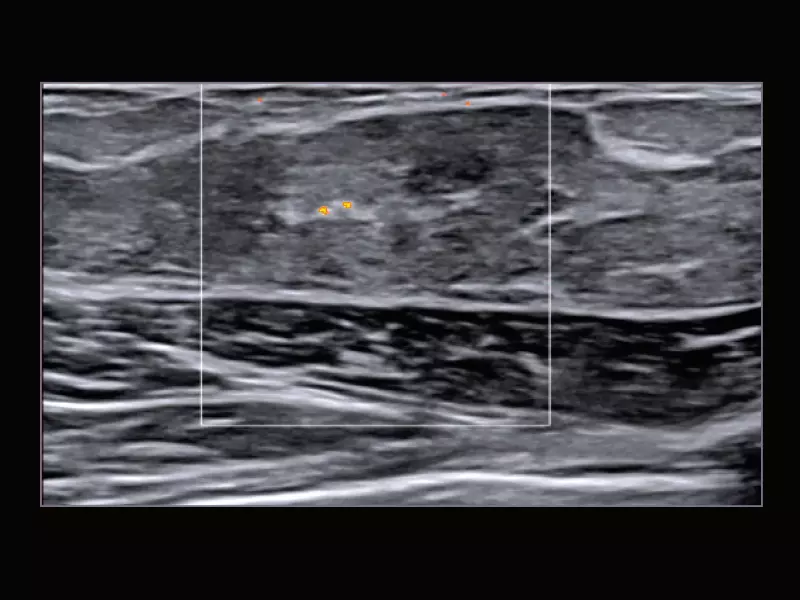

MyLab™C30 - Interventional B-Mode - Testis

MyLab™C30 - Interventional B-Mode - Testis